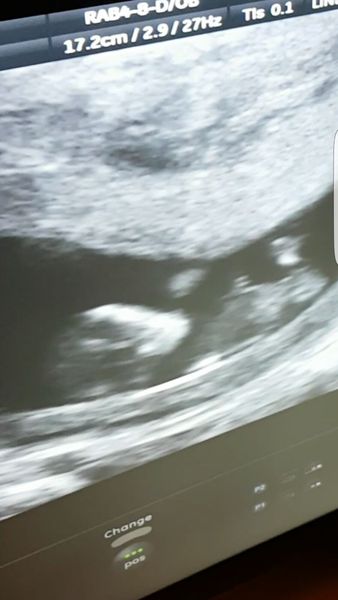

Wide awake again....anyone have any suggestions for insomnia? Forgot to put a picture of my latest scan earlier, the little one that makes all of this craziness 100% worth it

More scan waiting and symptom analysis from the December 2016 babies!

Scan is gorgeous, how amazing!